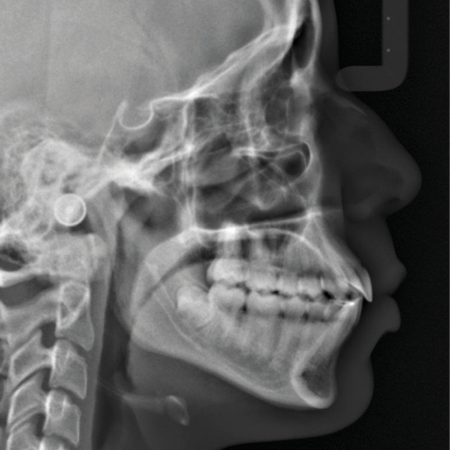

Desafios no tratamento de pacientes com discrepâncias verticais: abordagens clínicas com mini-implantes

INTRODUÇÃO: Os pacientes adultos têm, cada vez mais, buscado tratamentos ortodônticos sem recorrer à cirurgia ortognática. Em alguns casos, sejam eles de mordida aberta anterior ou de mordida profunda, é possível usar mini-implan...

Cirurgia Ortognática Mordida Aberta Ancoragem Ortodôntica Intrusão Dentária Mini-implantes

Desafíos en el tratamiento de pacientes con discrepancias verticales: abordajes clínicos con microimplantes

INTRODUCCIÓN: Cada vez más pacientes adultos buscan tratamiento de Ortodoncia sin recurrir a la cirugía ortognática. En algunos casos, ya sea mordida abierta anterior o mordida profunda, es posible utilizar microimplantes para propor...

Microimplantes Cirugía ortognática Mordida abierta Anclaje ortodóncico Intrusión dental